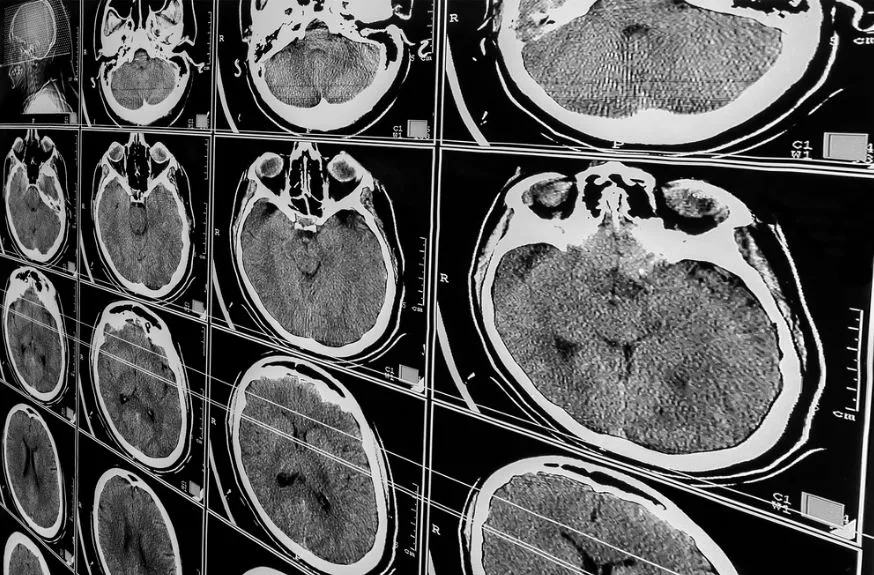

Initial scans or reports may not reflect the full extent of the damage. This gap between appearance and reality is one of the main reasons brain injury cases become more complex as time moves forward.

The Medical Reality That Changes Everything

Symptoms That Evolve Over Time

Brain injuries do not follow a fixed pattern. A person might improve for a short period and then experience setbacks. This shifting condition makes it harder to define the full impact early in the process.